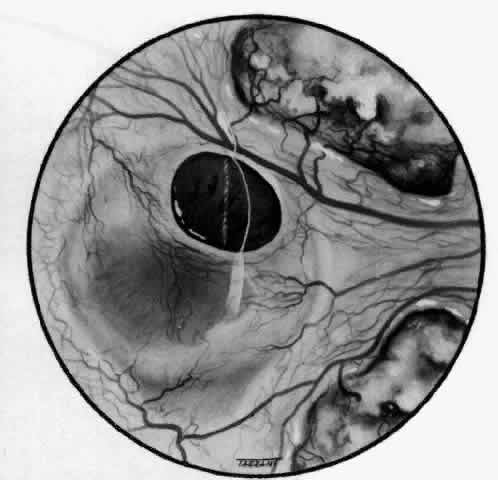

of the eye. A posterior scleritis often occurs as an extension of anterior

disease; but, as in Figure 20, most of the inflammation (in some cases all of the inflammation) is in

the posterior segment and the exudative detachments and subretinal granulomas

Fig. 20. Posterior scleritis. This eye was removed because of loss of vision and

pain, mistakenly diagnosed as malignant melanoma. (Courtesy of Professor N. Ashton) Fig. 20. Posterior scleritis. This eye was removed because of loss of vision and

pain, mistakenly diagnosed as malignant melanoma. (Courtesy of Professor N. Ashton)

|